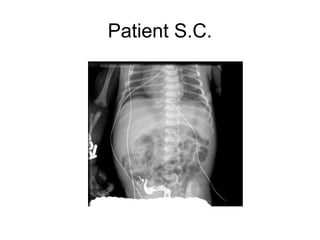

Patient S.C.

• Newborn male

• Full-term, uncomplicated vaginal

delivery

• Normal birth weight: 3115 g

Abdominal X-ray

• #5 Dilated small and large bowel loops, prominent transverse, descending, sigmoid